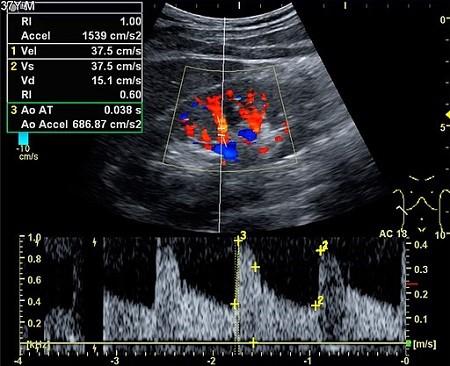

The sound waves may also be converted to colour pictures on a screen so that flow can be seen through the arteries or veins (colour Doppler) - as below.

Colour Doppler ultrasonography

© By Mikael Häggström [CC0] (Own work), via Wikimedia Commons

They may also be plotted on a graph showing changes in speed and direction (velocity).

The images below are produced from a Doppler scan of the kidney.

Kidney ultrasound scan

© By Kristoffer Lindskov Hansen, Michael Bachmann Nielsen and Caroline Ewertsen [CC BY 4.0 (https://creativecommons.org/licenses/by/4.0)], via Wikimedia Commons